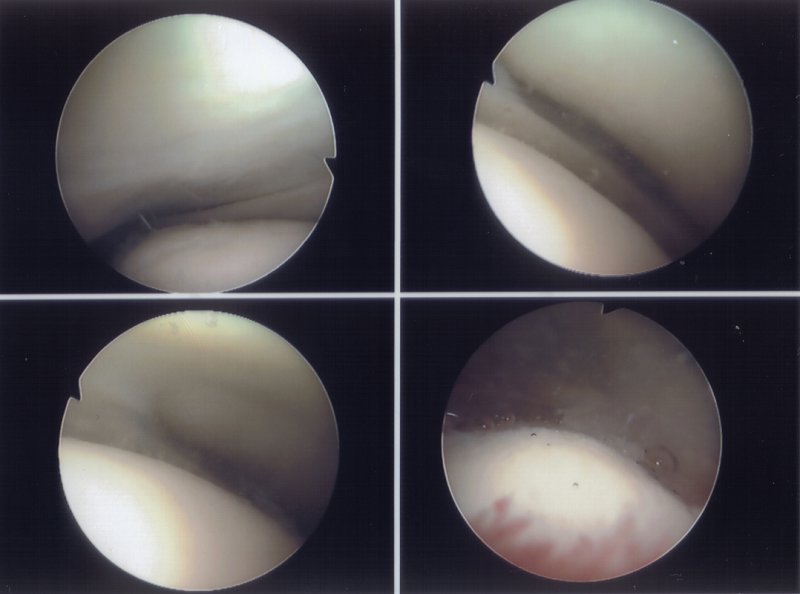

Heres the inners of my left knee. If anyone can make sense of it please share. I can tell you there is meniscus both sides in there somewhere.